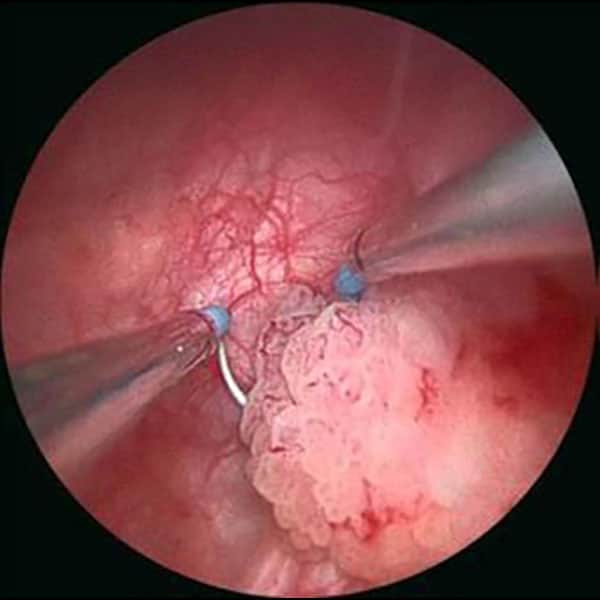

TUR-M ameliyatı, mesane kanserinin tanı ve tedavisinde kullanılan minimal bir cerrahi yöntemdir. Bu işlemde, üretra (idrar yolu) üzerinden bir alet (resektoskop) ile mesaneye ulaşılır ve tümörler çıkarılır. Ameliyat, kapalı olarak gerçekleştirilir. Ancak, bazı hastalar operasyon sonrası kanama, enfeksiyon veya idrar yolunda geçici sorunlar yaşayabilir. Bu nedenle, TUR-M ameliyatı sonrası dikkatli takip ve uygun tedavi önemlidir.

Mesane TUR ameliyatı sonrası yoğun bir kanama, normalde beklenmez. Eğer kanam varsa cerrahiden kaynaklanan bir sıkıntı vardır. Bu, genellikle mesanedeki doku ve damarların kesilmesi sırasında mühürlenen damar uçlarının tam olarak kapanmamasından veya damar uçlarının geri açılmasından kaynaklanır. Ameliyatın ardından mesanede iyileşme süreci başladığında, bazı hastalar idrarlarında hafif kanama görebilir. Bu durum genellikle geçici olup, iyileşme sürecinin bir parçası olarak kabul edilir.